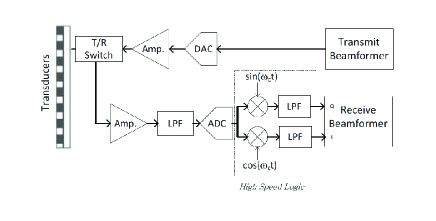

Note that sampling is performed in time, while our goal is to extract DFT coefficients. To this end, similarly to [5], we can use the Xampling mechanism proposed in [3]. A hardware Xampling prototype implemented by Baransky et al. in [11] is seen in Fig. 4.

The Xampling scheme allows to obtain coefficients from point-wise samples of the detected signal filtered with an appropriate kernel , designed according to the transmitted pulse-shape and the set . The required DFT coefficients are equal to the DFT of the outputs, therefore, the number of samples taken at each individual element is equal to the number of DFT coefficients that we want to compute. Hence, when we compute all nonzero DFT coefficients of the detected signal, - fold reduction in sampling rate is achieved without compromising image quality.

The entire scheme, performing low-rate sampling and frequency domain beamforming, is depicted in Fig. 6. Signals , detected at each transducer element, are filtered with an appropriate analog kernel and sampled at a low-rate, defined by the effective bandwidth of the transmitted pulse. Such a rate corresponds to the Nyquist rate of the baseband transmitted pulse. DFT coefficients of the detected signals are computed and beamforming is performed directly in frequency at a low-rate. This framework allows to bypass oversampling dictated by digital implementation of beamforming in time and to significantly reduce (up to -fold) the resulting sampling rate.

In our case, , defined in (28), is formed by taking scaled rows from an DFT matrix. It can be shown that by choosing rows uniformly at random for some positive constant , the measurement matrix obeys the RIP with high probability [19]. In order for this approach to be beneficial it is important to assume that . Since random frequency sampling is not practical from a hardware prospective, it is possible instead to sample a number of frequency bands, distributed randomly throughout the spectrum [11]. This approach is implemented in the board of Fig. 4.

As a next step we implemented low-rate frequency domain beamforming on an ultrasound imaging system [29]. The lab setup used for implementation and testing is shown in Fig. 8 and includes a state of the art GE ultrasound machine, a phantom and an ultrasound scanning probe. In our study we used a breadboard ultrasonic scanner with 64 acquisition channels. The radiated depth cm and speed of sound m/sec yield a signal of duration sec. The acquired signal is characterized by a narrow bandpass bandwidth of MHz, centered at a carrier frequency MHz. The signals are sampled at the rate of MHz and then are digitally demodulated and down-sampled to the demodulated processing rate of MHz, resulting in real-valued samples per transducer element. Linear interpolation is then applied in order to improve beamforming resolution, leading to real valued samples. Fig. 9 presents a schematic block diagram of the transmit and receive front-end of the medical ultrasound system being used.

At this point of our work, as illustrated in Fig. 10, in-phase and quadrature components of the detected signals were used to obtain the desired set of their DFT coefficients.